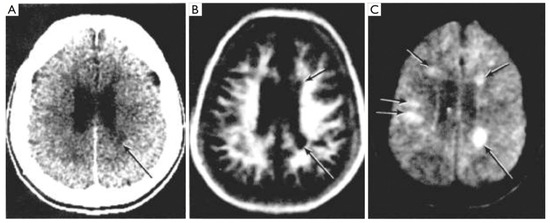

The contrast advantage of MRI was extended to included T2 dependent spin echo sequences in 1982 [8,9] (Figure 8) and further improvements in the demonstration of soft tissue contrast with MRI came with short inversion time IR (STIR) (Figure 9), diffusion-weighted, susceptibility-weighting (Figure 10) and T2-fluid attenuated inversion recovery (T2-FLAIR) (Figure 11) sequences [10,11,12,13]. In addition, from 1984 onwards Gadolinium based contrast agents (GBCAs) were used to create additional contrast in particular clinical situations [14,15] as shown in Figure 12. Imaging protocols using multiple sequences of these and other types have been established for different clinical applications and form the basis for modern MRI examinations of the brain and other organs of the body.

Figure 8.

Multiple sclerosis (MS): CT (A), inversion recovery (IR) (B) and long TR, long TE spin echo (SE) (C) (July 1982) [8]. A single MS lesion is seen on the CT image (arrow) (A). This is also seen on the IR and SE images (arrows). There are an additional four lesions seen on the SE image (C) in normal appearing white matter on the CT image (A).